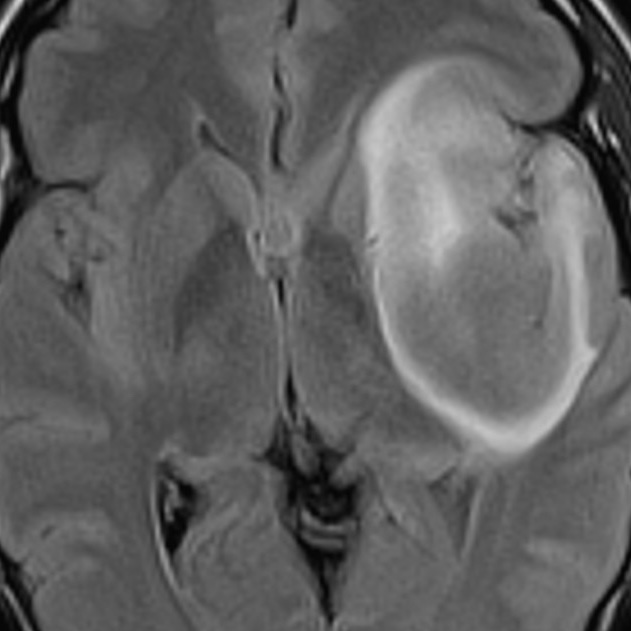

Beautiful example of T2-FLAIR mismatch in a proven IDH-mutant astrocytoma. Central FLAIR suppression with a hyperintense peripheral rim. Suggestive of IDH-mutant astrocytoma (but can also be seen in diffuse astrocytoma MYB or MYBL1 altered and angiocentric glioma).